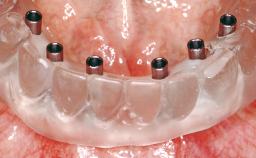

A 63-year-old male patient was referred for a consultation and treatment of partial edentulism in the maxilla. The patient presented with residual anterior teeth and declined a partial removable prosthesis. He reported that the maxillary posterior teeth had been extracted due to mobility and periodontal disease two months before the consultation. The patient’s chief complaint was that his residual maxillary teeth were mobile and that he was unable to chew. The patient’s desire was a stable and comfortable fixed maxillary rehabilitation. The patient was a light smoker (fewer than 10 cigarettes/ day), and his medical history was without significant findings. He was not on any regular medication at the time of consultation. The extraoral examination revealed a normal physiognomy with a correct distribution of the facial thirds. The patient presented a low lip line, and the transition line between teeth and soft tissues was not exposed during a forced smile.

# of Implants 6

Modality 6+ implants with immediate loading

Loading Protocol Immediate

Provisional Implant-Supported Prosthesis Prosthodontic margin < 3 mm apical to mucosal crest Prosthodontic margin < 3 mm apical to mucosal crest